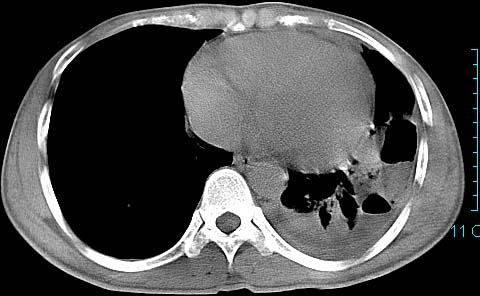

以下是引用ctkz987在2006-3-28 13:04:00的发言:[br]左侧胸腔积液穿刺后多发气液平(多房性),结合临床有高热不除外合并感染。

以下是引用qian在2006-3-28 14:32:00的发言:[br]左肺下叶大片状阴影,密度不均,见有条片影和空洞及气液平,少量胸腔积液伴有胸膜增厚,从图像看积液密度比水的密度高,结合病史,考虑左下肺化脓性炎症伴有脓胸。

以下是引用wawaquan在2006-3-28 22:25:00的发言:[br]左上肺舌段多发斑片影。结合“男24y咳嗽咳痰气促伴高热(38.5--39.5)20多天”及穿刺史,[br]考虑1 左下肺化脓性炎症;2脓胸。

以下是引用乡医在2006-3-28 18:37:00的发言:[br]左侧多发液气平面结合患者男24y咳嗽咳痰气促伴高热(38.5--39.5)20多天,查胸水:ldh239.3,总蛋白59.19,tb-ab阴性,利凡它试验+,红c2.7*109,白c1.08*109,分类淋巴92%分叶8%,考虑1脓胸2肺隔离征感染